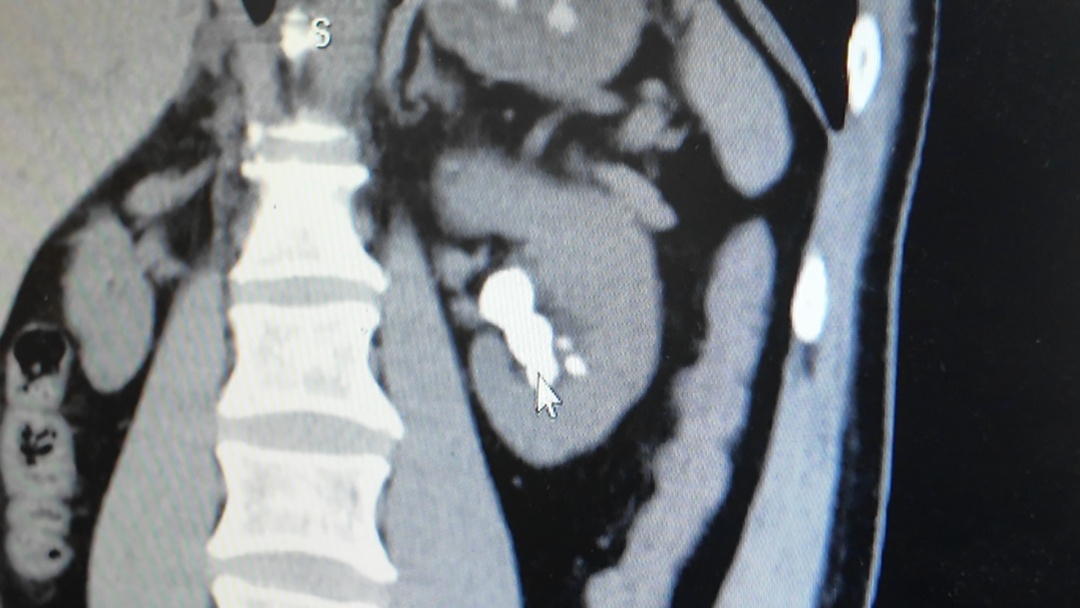

经过CT检查

确诊为尿路结石